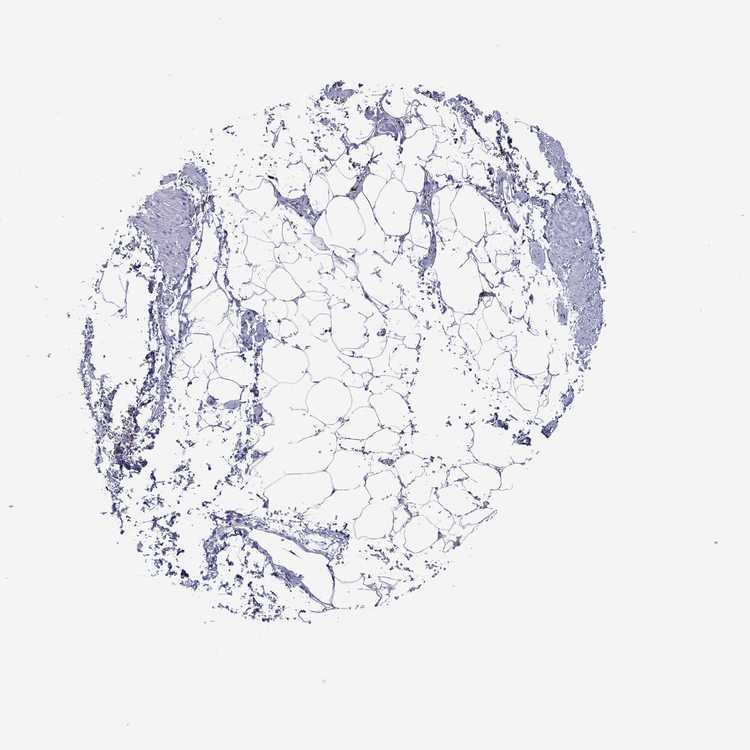

SOFT TISSUE 1 - Antibody stainingi

Antibody staining in the annotated cell types in the current human tissue is reported as not detected, low, medium, or high, based on conventional immunohistochemistry profiling in selected tissues. This score is based on the combination of the staining intensity and fraction of stained cells.

Each image is clickable and will lead to virtual microscopy that enables deeper exploration of all samples and also displays staining intensity scores, fraction scores and subcellular localization as well as patient and tissue information for each sample.

Antibody HPA045827Antibody HPA072480

Chondrocytes Low-

Fibroblasts Not detected-

Peripheral nerve Not detectedNot detected

SOFT TISSUE 2 - Antibody stainingi

Fibroblasts Not detectedNot detected